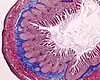

| Eosina | Ácida / Basofílica | Tiñe proteínas y estructuras con afinidad por los ácidos en diferentes tonos de rojo | Tinción histológica general | ![]() |